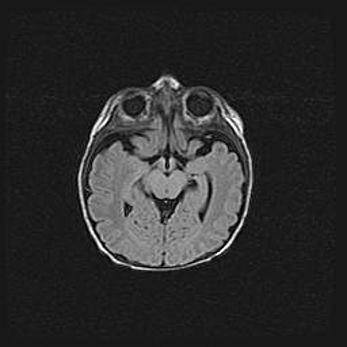

Множественные кисты обоих полушарий головного мозга, наибольшая из них в правой затылочной области. Ассиметричная атрофическая гидроцефалия.

Возраст: 7 месяцев

Вес: 5660 г

Пол: мужской

Окружность головы: 41,5 см

Срок гестации: 28-29 недель

Кисты головного мозга развиваются в результате многоочаговых некрозов вещества мозга и возникают вследствие перенесенной перинатальной инфекции, менингитов, энцефалитов, асфиксии, родовой травмы, расстройств мозгового кровообращения различного генеза. Образованию кист в веществе головного мозга плодов и новорожденных способствуют такие факторы, как высокое содержание в нем воды, недостаточная (или отсутствие) миелинизация и слабая астроглиальная реакция на повреждение.

Кисты могут сочетаться с гидроцефалией и другими поражениями головного мозга.